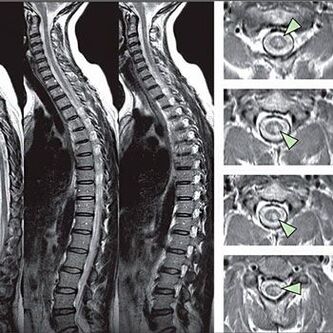

Norint nustatyti jautrumo sutrikimų požymius, atliekami specialūs funkciniai testai. Informatyviausias instrumentinių metodų diagnozavimo pasirinkimas yra X -LAY veikimas. Tačiau atliekant išsamų stuburo tyrimą, dažnai atliekami MRT ir KT. Įtariant dėl širdies ir kraujagyslių sistemos ligų, pacientui rekomenduojama atlikti EKG procedūrą.